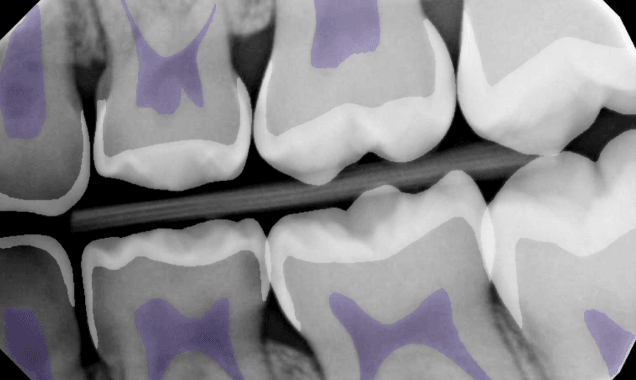

PULP & ENAMEL

6/7Overjet AI outlines enamel and pulp to help dentists evaluate tooth structure, educate patients, and assist clinics in comprehensive charting functions.Colorizing enamel and pulp enhances image evaluation by vividly illustrating their interrelation and aiding in comprehensive insights.